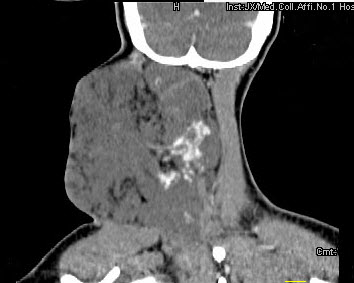

女,32岁,颈部包块8年余,包块逐渐长大,CT如图所示,最可能的诊断为()。

A:颈部神经纤维瘤

B:颈部横纹肌肉瘤

C:颈部巨大血管瘤

D:颈部神经鞘瘤

E:颈部异位甲状腺